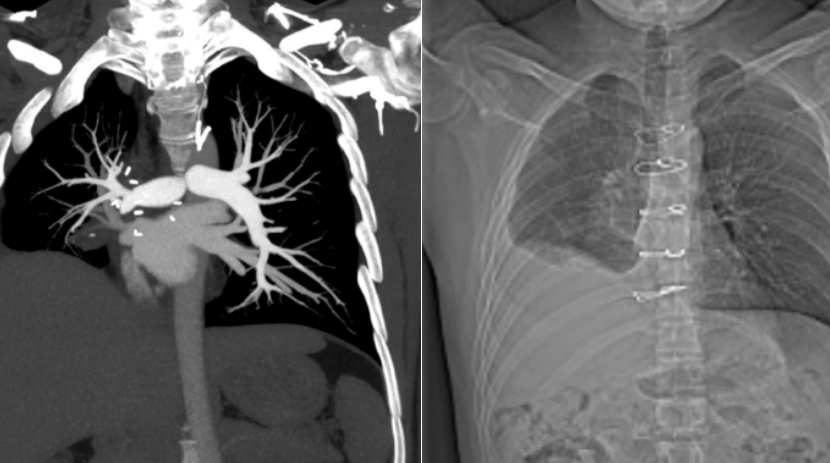

A 28-year-old man had a tumor that grew in his lung, extended to his heart, and then was washed down in the bloodstream to his brain, kidney, intestines and coronary arteries. The repeated episodes of tumor embolism made chemotherapy impossible, and the surger...